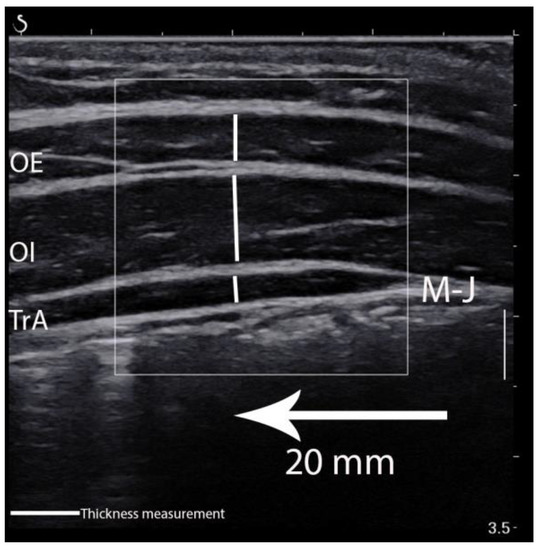

LAMs elasticity was calculated in the ultrasound scanner using the Q-Box quantitative tool after collecting all data (Figure 2). This was used to quantify each muscle shear modulus. Three separate circles were positioned inside the fascial edge of each muscle, and the muscle elasticity within the circle was automatically calculated and depicted in kilopascal (kPa). The mean value of the three separate circles was considered the muscle elasticity value from a given image [16]. In turn, images for LAMs thickness and superficial fat layer measurements were edited and calculated using RadiAnt Dicom Viewer 5.5.1 (Medixant, Poznań, Poland). The edits included enlarging, brightening, and adding contrast. The vertical marking line positioned 20 mm from the musculofascial junction of the TrA was consistently used to re-measure the thickness for each muscle (Figure 3). The vertical distance between the musculofascial layers represented the individual thickness of the oblique external (OE), oblique internal (OI), and TrA [24,30].

Figure 3.

Thickness measurement of the lateral abdominal muscles. OE—oblique external; OI—oblique internal; TrA—transversus abdominis muscle; M-J—myofascial junction of the TrA.